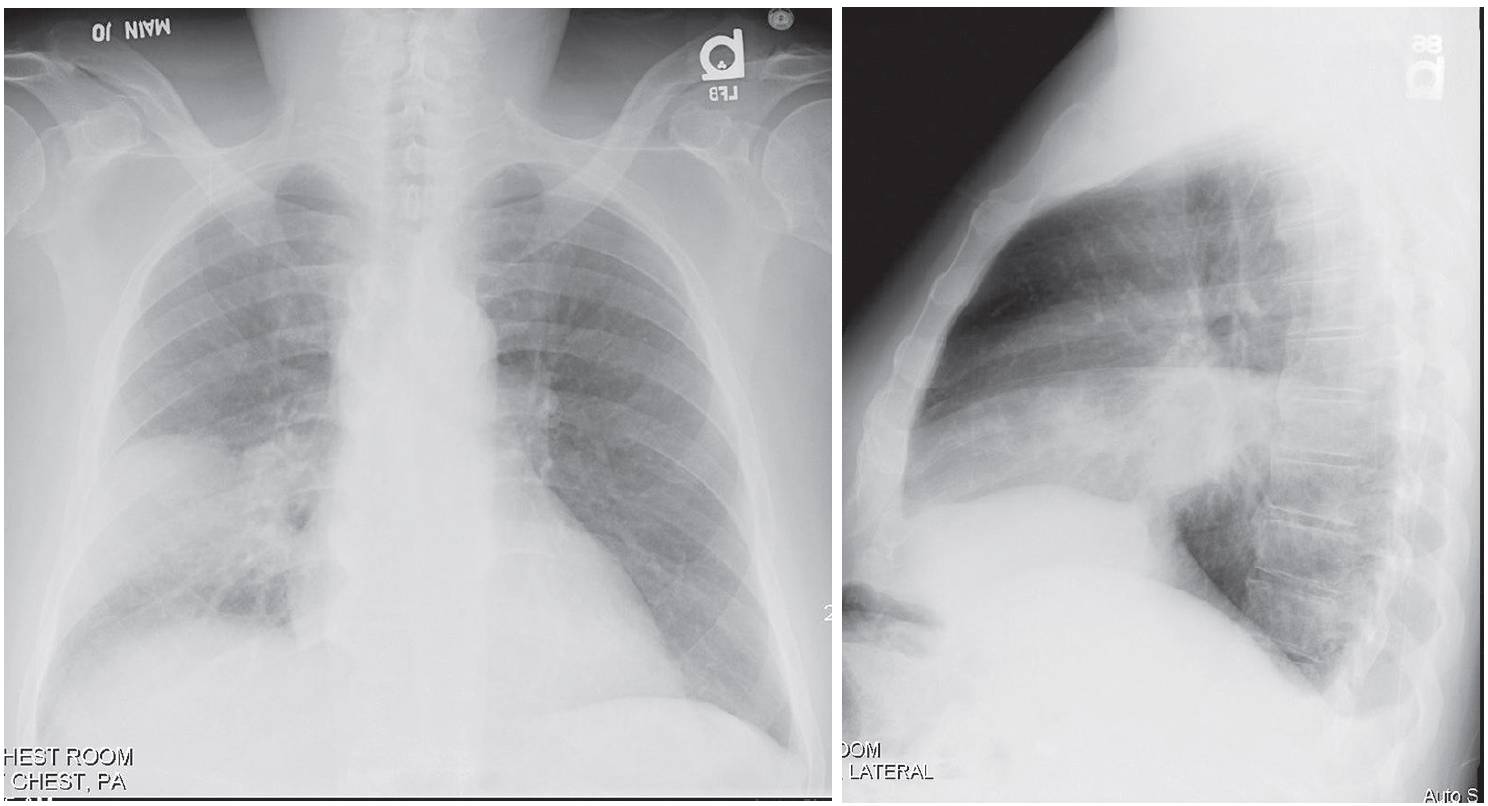

PA and lateral chest X-rays reveal dense, non-segmental homogeneous lobar consolidation that partially silhouettes the right heart border and is bordered by the horizontal and oblique fissure. No associated volume loss. A small ipsilateral pleural effusion blunts the posterior sulcus.

Pneumococcal Pneumonia; Right Middle Lobe

- Homogeneous, non-segmental, parenchymal consolidation involving one lobe; multi-lobar involvement less common

- Air space disease abuts surrounding visceral pleura of fissural surfaces

- Predilection for lower lobes or posterior segments of upper lobes

- Minimal volume loss

- Air bronchograms common

- Pleural effusion common (60%); empyema unusual